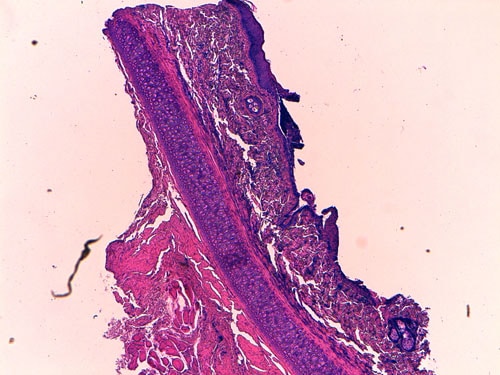

- les biopsies cutanées (LAPVSO) montrent également des vésiculo-pustules contenant des cellules acantholytiques, ainsi que des éléments PAS-positifs au sein des croûtes, évoquant fortement des hyphes mycéliennes (Photos 6 à 8).

Biopsie d’une lésion pustuleuse du pavillon auriculaire (X40, LAPVSO) Visualisation de cellules acantholytiques (X400, LAPVSO) Visualisation d’hyphes mycéliennes dans les couches superficielles (X1000 PAS, LAPVSO)

Photos 6 à 8 : Examen histopathologique montrant l’acantholyse dans les pustules et les hyphes mycéliennes au sein des croûtes - la recherche virale sur biopsie cutanée (PCR, Scanelis) est négative pour l’herpesvirose